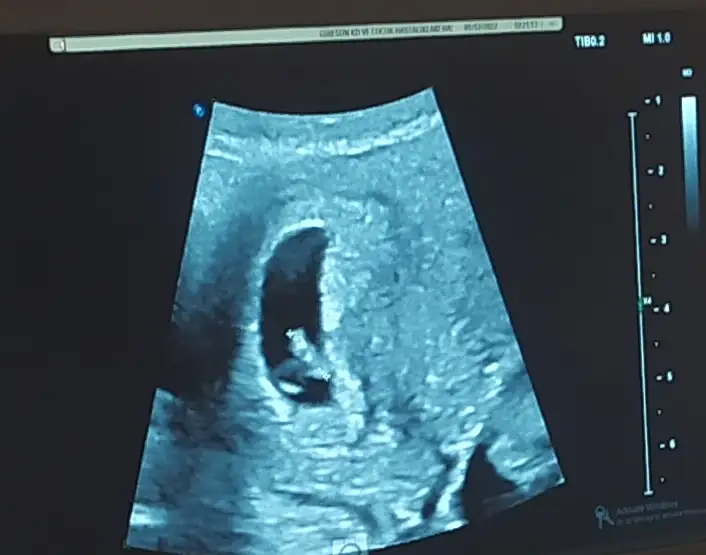

Bak mesela ilk foto oğlumun ilk ulturoson resmiydi ikincisi simdikinin ilk kese fotoğrafiGeçen sefer doktorum dördüncü aya kadar kız demişti ben aldım kıyafetleri felan pembiş pembiş bir ay sonra kontrole bi gittim dedi kız değil erkekşaşkınlıktan inanmamıştım hep kız istiyordum çünkü bide başta kız deyince dönmez artık demiştim ama oluyormuş bazen saklıyormuş bakalım bu sefer de gönlüm kızdan yana ama nasip

Durduğu yere göre mi belli oluyor cinsiyeti ben hiç anlamıyorum daBak mesela ilk foto oğlumun ilk ulturoson resmiydi ikincisi simdikinin ilk kese fotoğrafi

O zaman senin kız geliyorBak mesela ilk foto oğlumun ilk ulturoson resmiydi ikincisi simdikinin ilk kese fotoğrafi

Fasulye tuttu oğlum oldu simdikide yuvarlak bakalım kizmi olucakO zaman senin kız geliyorşuan keseler farklı çünkü birbirinden. Bakalım kese teorisi tutacak mı Yuvarlak olunca kız fasulye gibi olunca erkk diyorlar ya